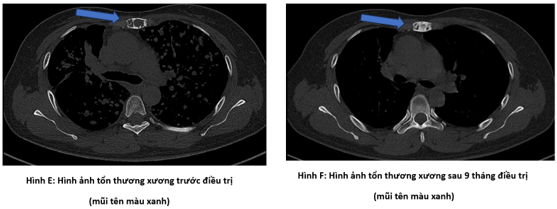

Bệnh nhân đi khám tại bệnh viện Bạch Mai được chụp cắt lớp vi tính lồng ngực phát hiện nhu mô thùy trên có khối đặc kích thước 40 x 35mm, các nốt đặc đường kính <12mm lan tỏa nhu mô hai phổi, ổ tiêu xương ức kích thước 31 x 13mm.

Hình 1: Hình ảnh tổn thương phổi trước điều trị: nhu mô thùy trên có khối đặc kích thước 40 x 35mm (mũi tên màu đỏ), các nốt đặc đường kính <12mm lan tỏa nhu mô hai phổi (mũi tên màu xanh)